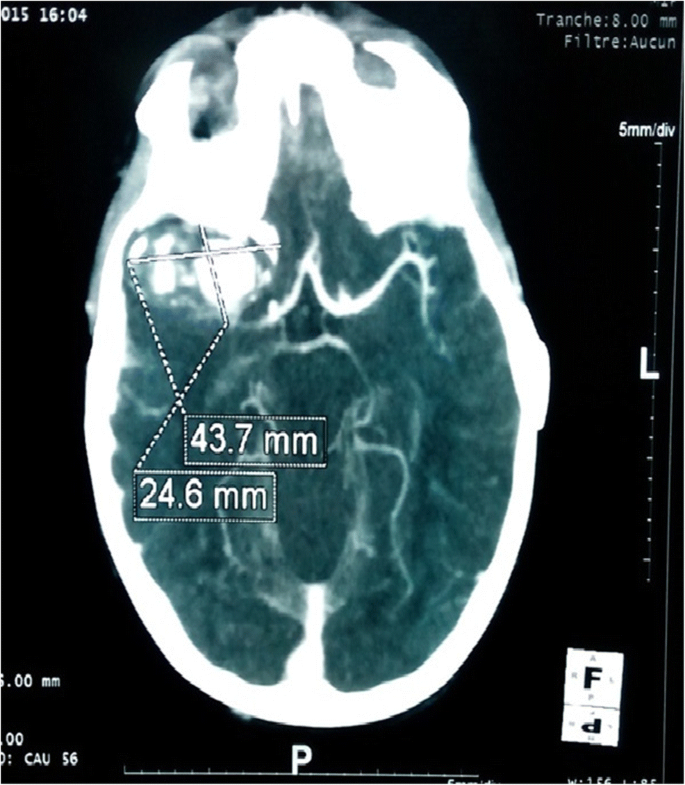

Pediatric Intracranial Aneurysms In Senegal A Series Of 10 Cases Treated In Unfavorable Socio Economic Conditions Springerlink